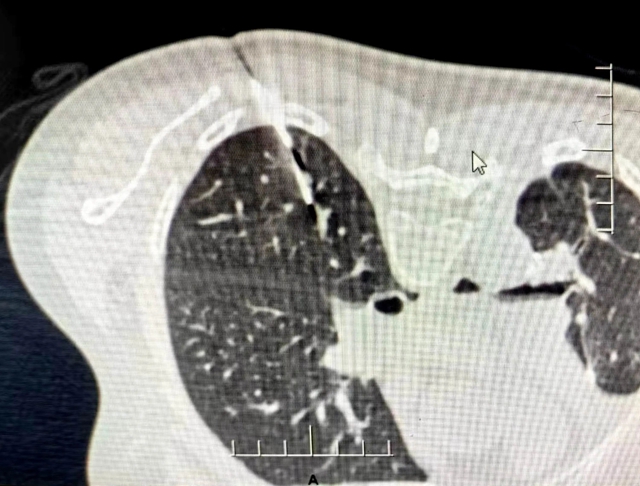

不幸的是,今年2月底右下肺又新长出6mm的肺癌。因为朱阿姨已经历过两次外科手术,切除了三“块”肺组织,如果再次外科手术治疗,显然不是最好的选择,这个时候到底改怎么治疗成为摆在医生面前的难题。

右下肺6mm肺癌,如箭头所示,不易发现

“近年来,肿瘤消融治疗发展迅速,已成为继手术、放疗、化疗、靶向治疗和免疫治疗之后又一重要的肺癌治疗手段。”西南医科大学附属医院呼吸与危重症医学科黄成亮副教授介绍,肺癌微波消融治疗通俗来讲,也可以叫一针“烧死”肺癌,就是把微波消融针,在CT引导局部麻醉下,穿刺到肺癌病变区域,通过微波产生的高温,在几分钟内使肺癌细胞发生凝固性坏死,类似于微波炉加热饭菜一样。微波消融后,在病灶周围形成1cm以上的毛玻璃影,往往表明这个肿瘤被完全杀灭。

由于肺时时刻刻在呼吸,而下肺的呼吸运动比较大,且病灶只有6mm,挑战性极大,黄成亮副教授在CT引导下,精准的把一根直径约2mm的消融针插入肿瘤病灶,很快消灭掉了右下肺的肿瘤。手术助手张明博士配合完美,消融结束后再次进行CT检查,确保病灶已经被灭活杀死,最终手术圆满成功。